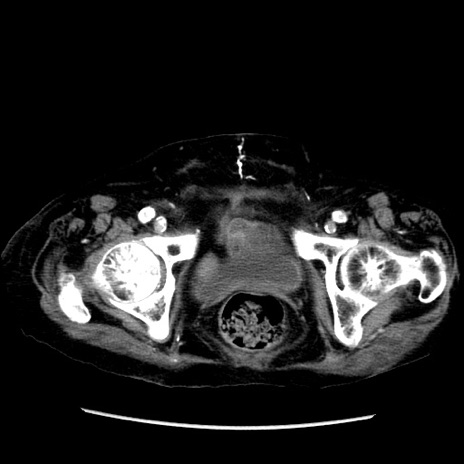

症例14(横断像)

【症例】 90歳代女性

【主訴】 腹痛・嘔吐

【現病歴】今朝から左側腹部痛を認めた。 経過観察していたが、嘔吐を認めたため来院。

【既往歴】 子宮癌術後

【身体所見】 意識清明、BP 127/54mmHg、P 98bpm Sp02 95%(RA)、BT 35.8°C、腹部平坦・軟腸ぜん動音聴取良好、右下腹部圧痛(+) 反跳痛なし

【データ】WBC 9800、CRP 0.46